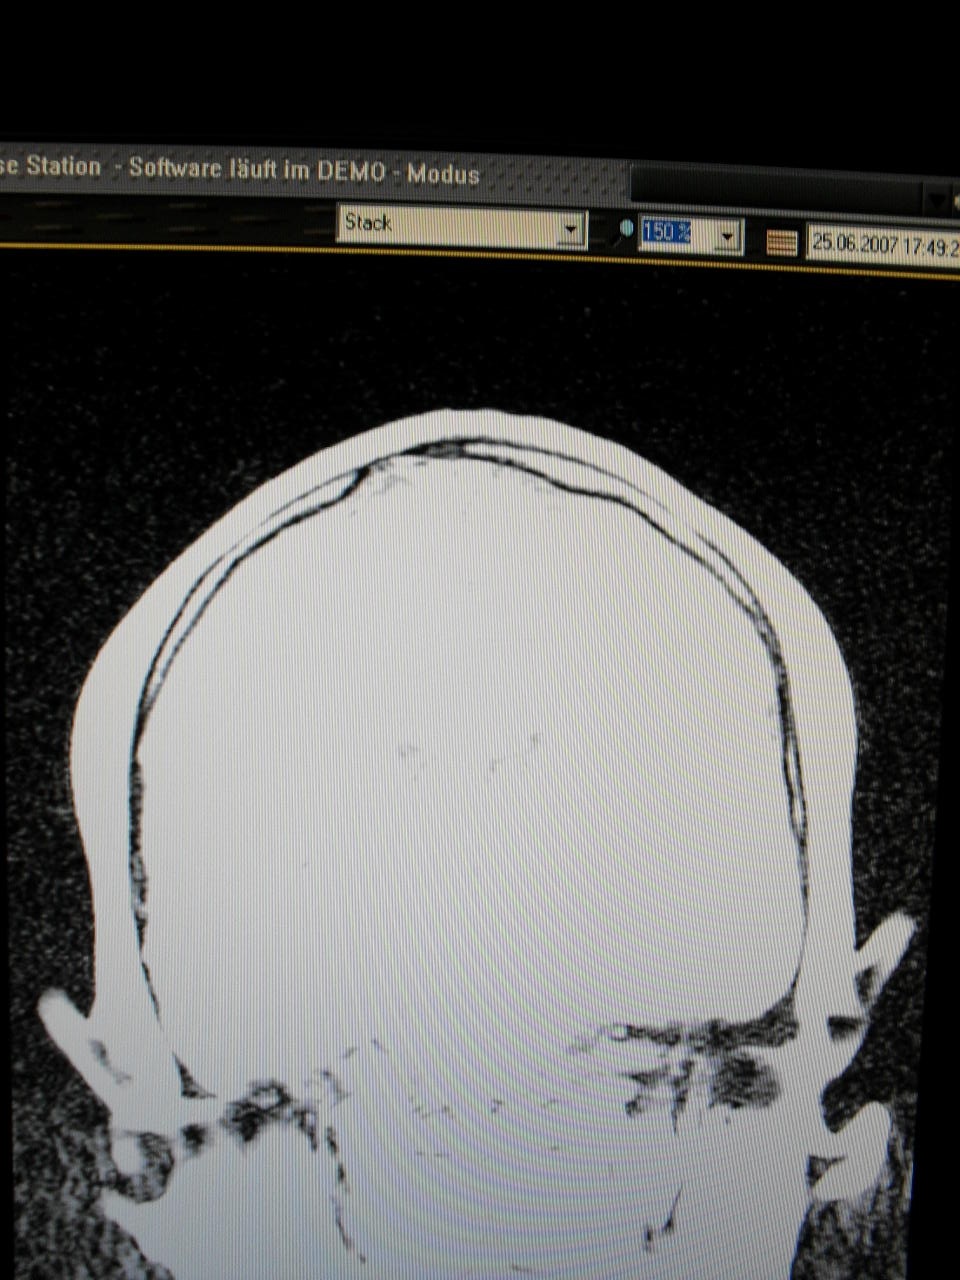

War auch schon paar mal in der Neurochirugie,weil ich probleme habe,da mir auf meiner Birne eine Knochenleiste nach oben heraus steht!

Jedenfalls bin ich mit meinen Nerven am Ende...und will euch mal paar Bilder von meinen MRT zeigen,weil ich der Meinung bin,das es dort diverse Auffälligkeiten nach meinen Standpunkt aus gibt!

Vorn weg möchte ich noch sagen,das ich denke...,das ich unter einen Kindlichen SHT leide,und meine Weichteile angegriffen sein müssen...."dura Mater"....äussere harte Hirnhaut....muss einen weg bekommen haben.

Hier die Bilder...